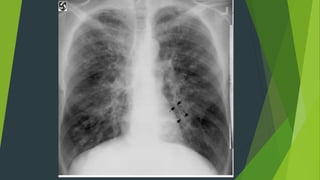

Các dạng tổn thương

- Hình ảnh kính mờ (verre dépoli)

- Nốt mờ nhỏ (hạt kê)

- Hình ảnh mờ dạng lưới

- Hình ảnh lưới_nốt (réticulo_nodulaire)

- Hình ảnh nốt mờ lớn và khối mờ

- Hình mờ tổ ong

Đặc điểm tổn thương

Mờ rõ nét

Không tập trung

Không có dạng thùy, phân thùy

Không có hình ảnh phế quản khí

Tiến triển chậm